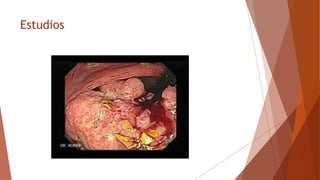

Estudios